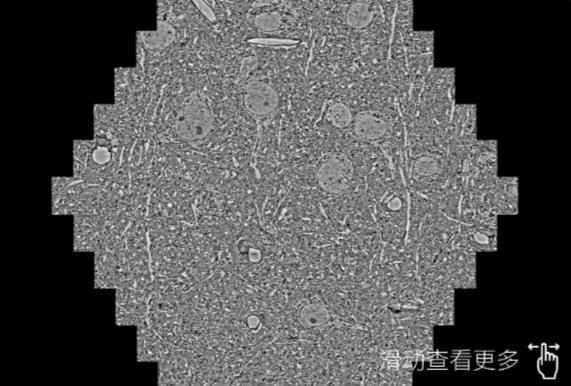

鼠脑切片。左图使用铜梁蔡司铜梁扫描电镜MultiSEM706对165μmx143pm面积区域成像,耗时仅需1.5秒。右图为鼠脑切片中30μm区域放大效果。样品由芝加哥大学B.Kasthuri提供。

使用蔡司高速铜梁扫描电镜MultiSEM对1mm²人脑皮层组织进行高分辨成像,并对其中的各种细胞结构进行三维重构分析。左图展示了2x3mm²组织平面中锥体神经元的三维重构效果。右图显示了局部体积神经元三维重构。图像由哈佛大学chtman实验室提供,渲染图由D. Berger 制作。